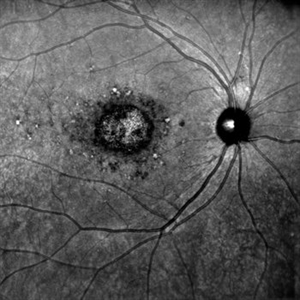

Stars of Stargardt

Aug 4 2025 by Malvika Singh

Infrared fundus photograph of a 22 year old female with Stargardt's disease.

Photographer: Dr Malvika Singh, Retina Foundation, Ahmedabad, India

Imaging device: Mirante SLO/OCT

Condition/keywords: infrared image, Stargardt disease